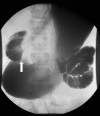

Background: Superior mesenteric artery (SMA) syndrome is an uncommon condition resulting in partial small bowel obstruction because of external compression of the third portion of the duodenum between the SMA anteriorly and the aorta posteriorly. SMA syndrome often presents with postprandial nausea, bilious vomiting, and abdominal pain with associated weight loss. Onset of symptoms can be acute (occurring in the setting of rapid weight loss because of trauma/surgery) or can be vague and chronic over many years.

Case reports: We present two cases of female adolescents who presented with symptoms of duodenal obstruction attributed to SMA syndrome. Both failed conservative treatment with weight gain and underwent successful laparoscopic duodenojejunostomy procedures with resolution of duodenal obstruction.

Conclusion: In the differential diagnosis of persistent nausea and bilious vomiting, even in the setting of an eating disorder, SMA syndrome should be considered. Upper gastrointestinal examination is the primary modality for diagnosing SMA syndrome, but ultrasound is an inexpensive, rapid screening tool for patients with unexplained abdominal pain. Abdominal computed tomography may also be helpful in selected patients. Conservative therapy consisting of nutritional support to enhance weight gain is usually sufficient and is accomplished with placement of a nasojejunal feeding tube past the point of duodenal compression. When conservative therapy fails, laparoscopic duodenojejunostomy can provide definitive relief of the obstruction.